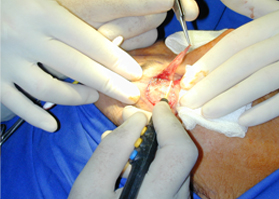

經(jīng)典案例

手術(shù)圖片